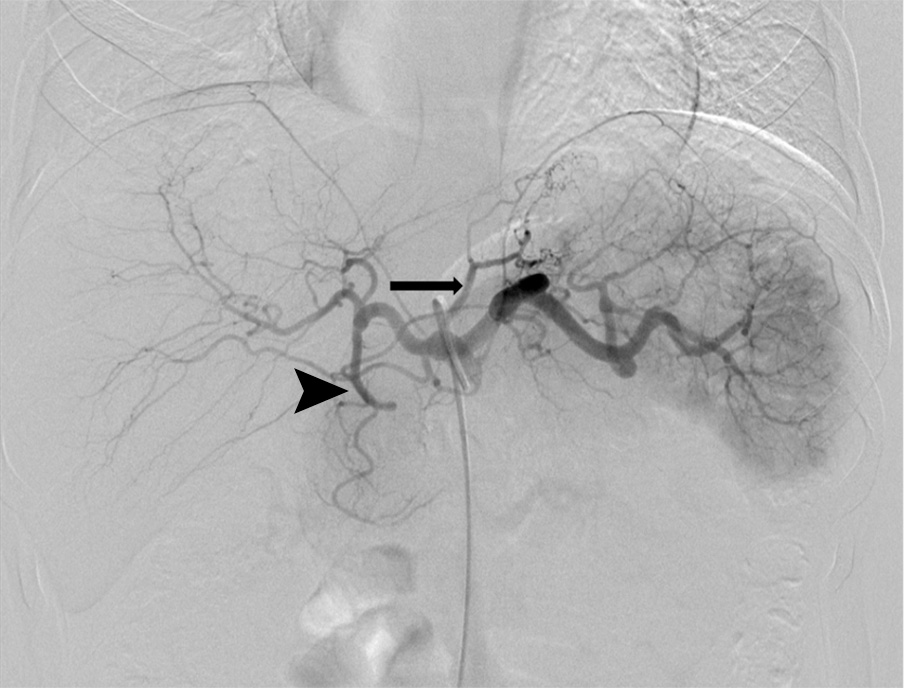

Example of bariatric embolization

Example of bariatric embolization in a 32-year-old African American woman with a starting weight of 253 lb and a starting BMI of 47.8 kg/m2. She demonstrated an 8.8-lb weight loss from the 1-week baseline, a 12-lb weight loss from baseline 2 weeks after bariatric embolization, and an 18.2-lb weight loss from baseline at 12 weeks. This represents a 12.3% of loss of excess body weight at 12 weeks and a 12-week BMI of 44.4 kg/m2.